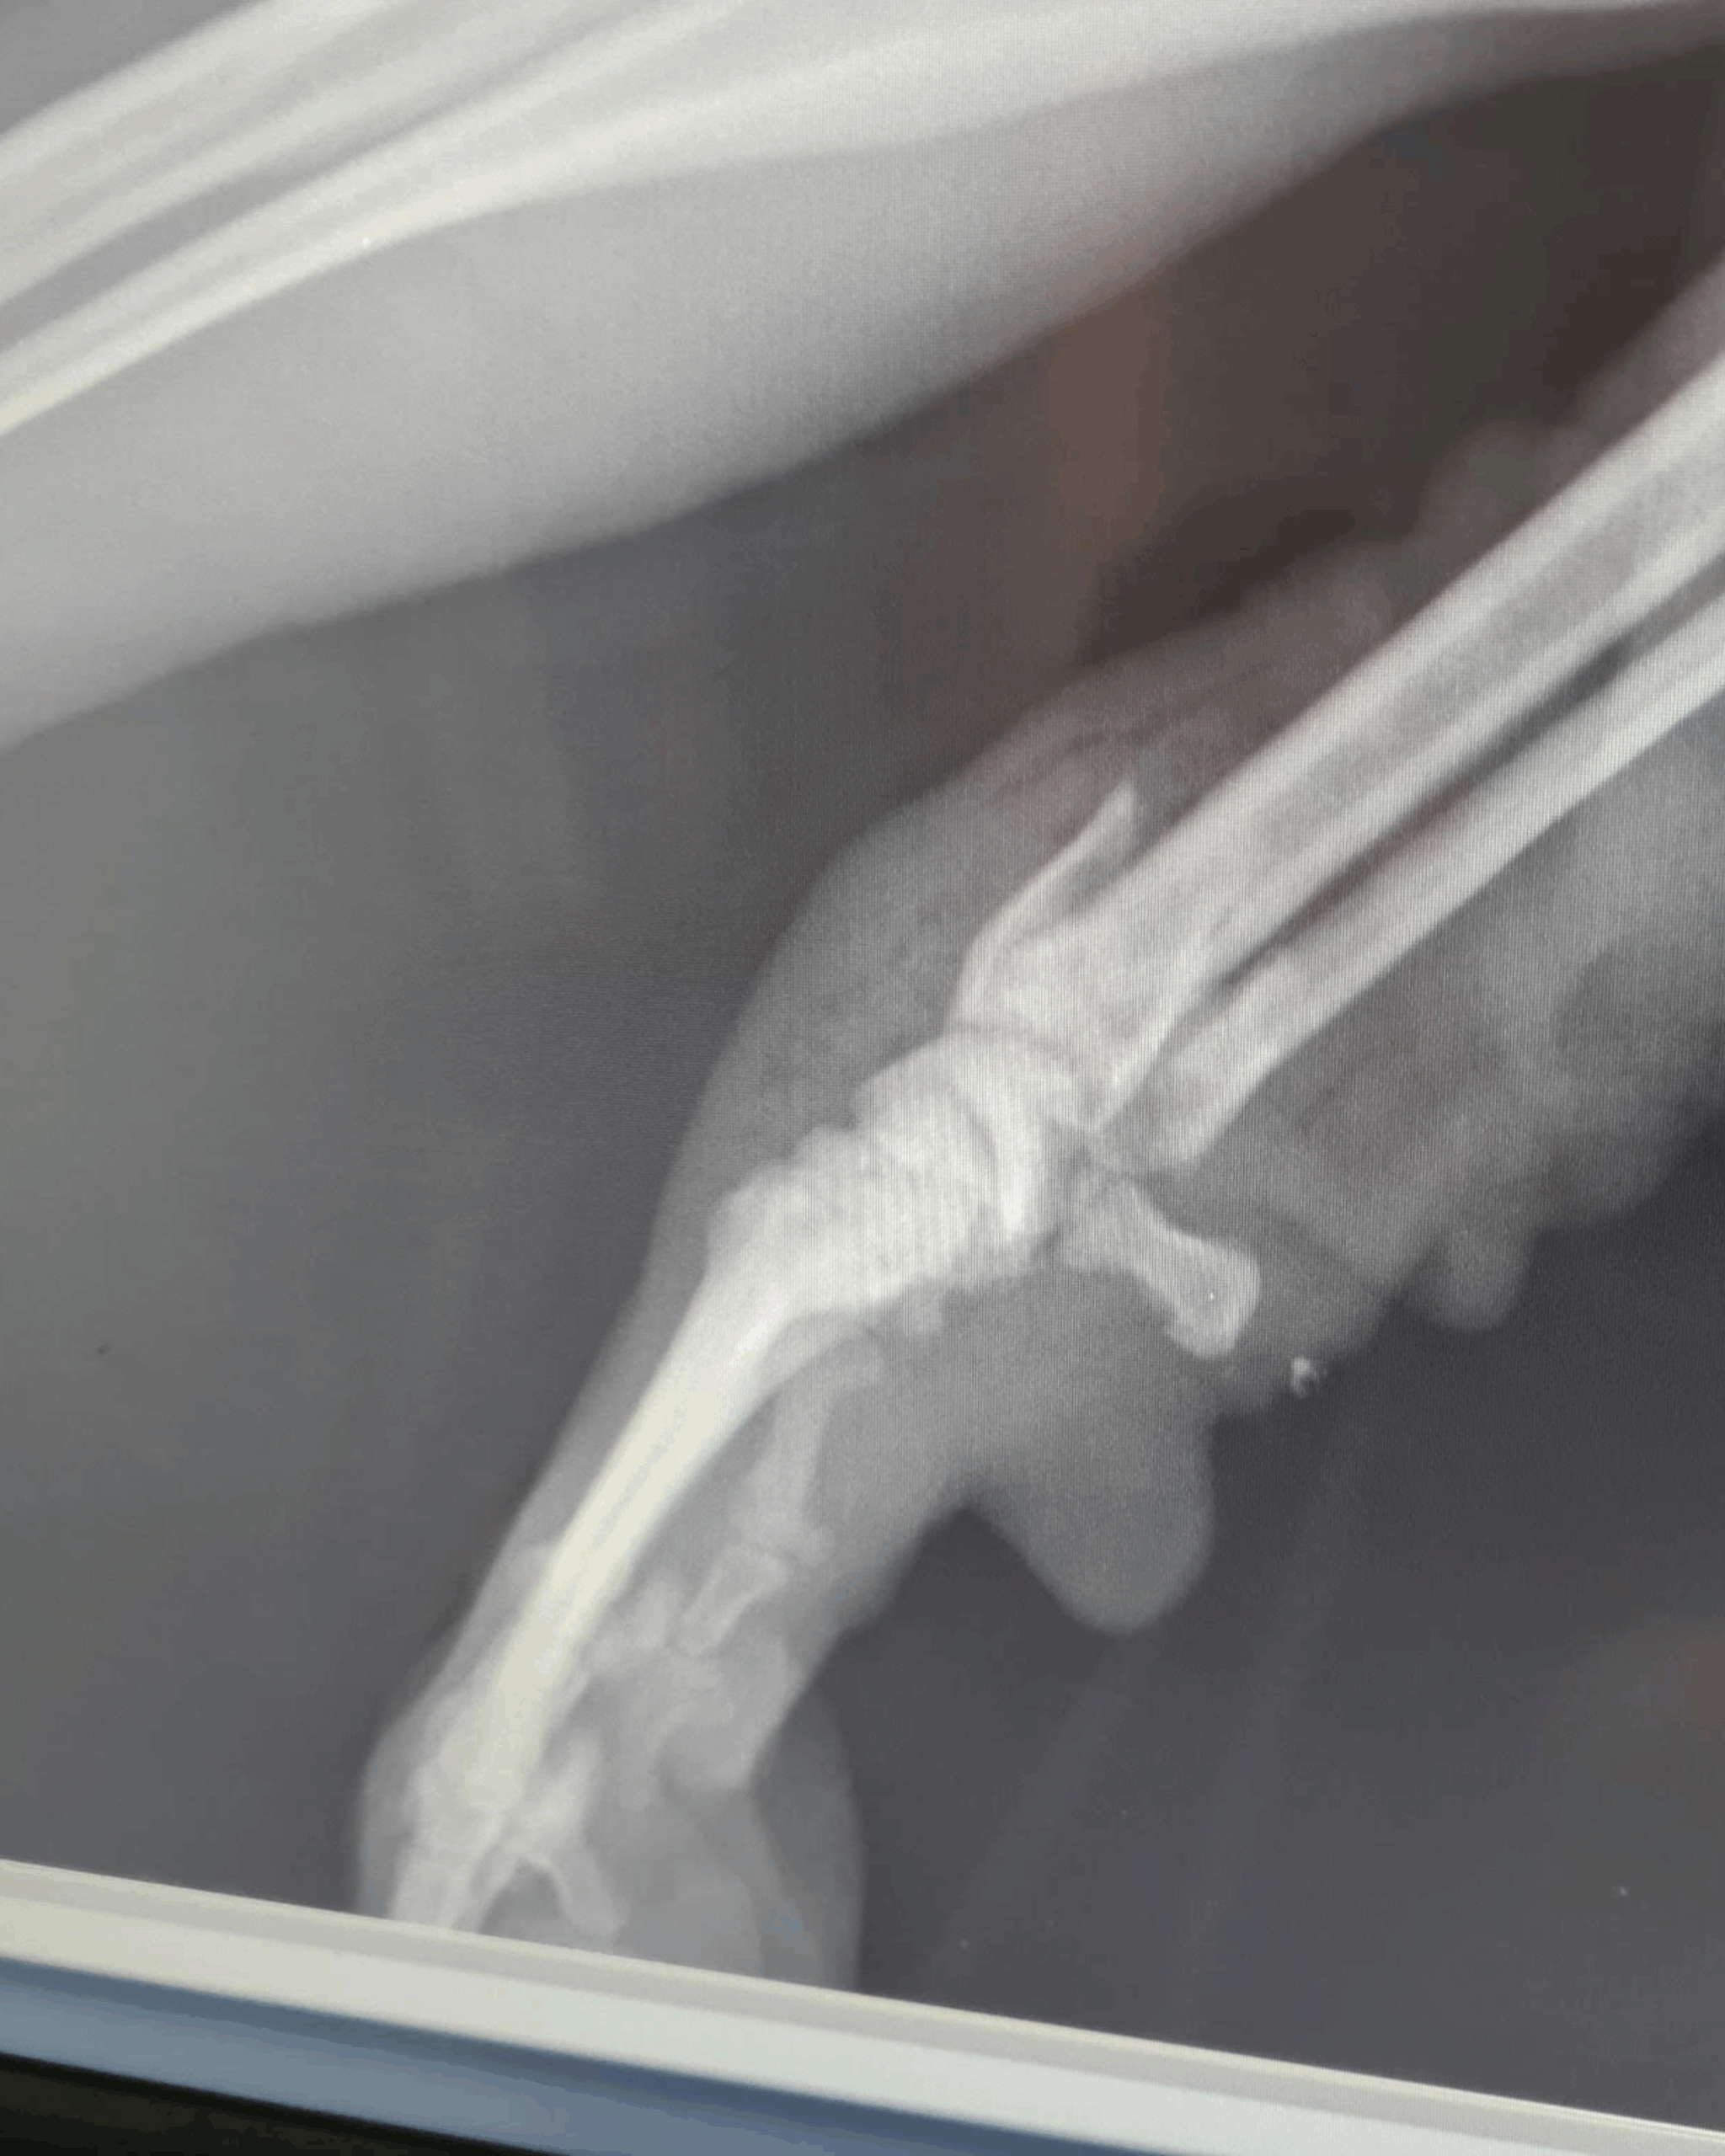

Dodatkowo zdiagnozowano u niego babeszjozę – chorobę odkleszczową. Kleks miał złamania obu kończyn: przedniej lewej (kość łokciowa i promieniowa) oraz tylnej prawej (panewka stawu biodrowego). Początkowo musiał zostać ustabilizowany, zanim możliwe były operacje. 3 marca poskładano jego łapę, a 11 marca zoperowano miednicę. Pogruchotaną kość udało się złożyć, a głowę kości biodrowej częściowo usunięto – pęknięcie panewki mogłoby powodować dalsze problemy i konieczność kolejnych zabiegów.